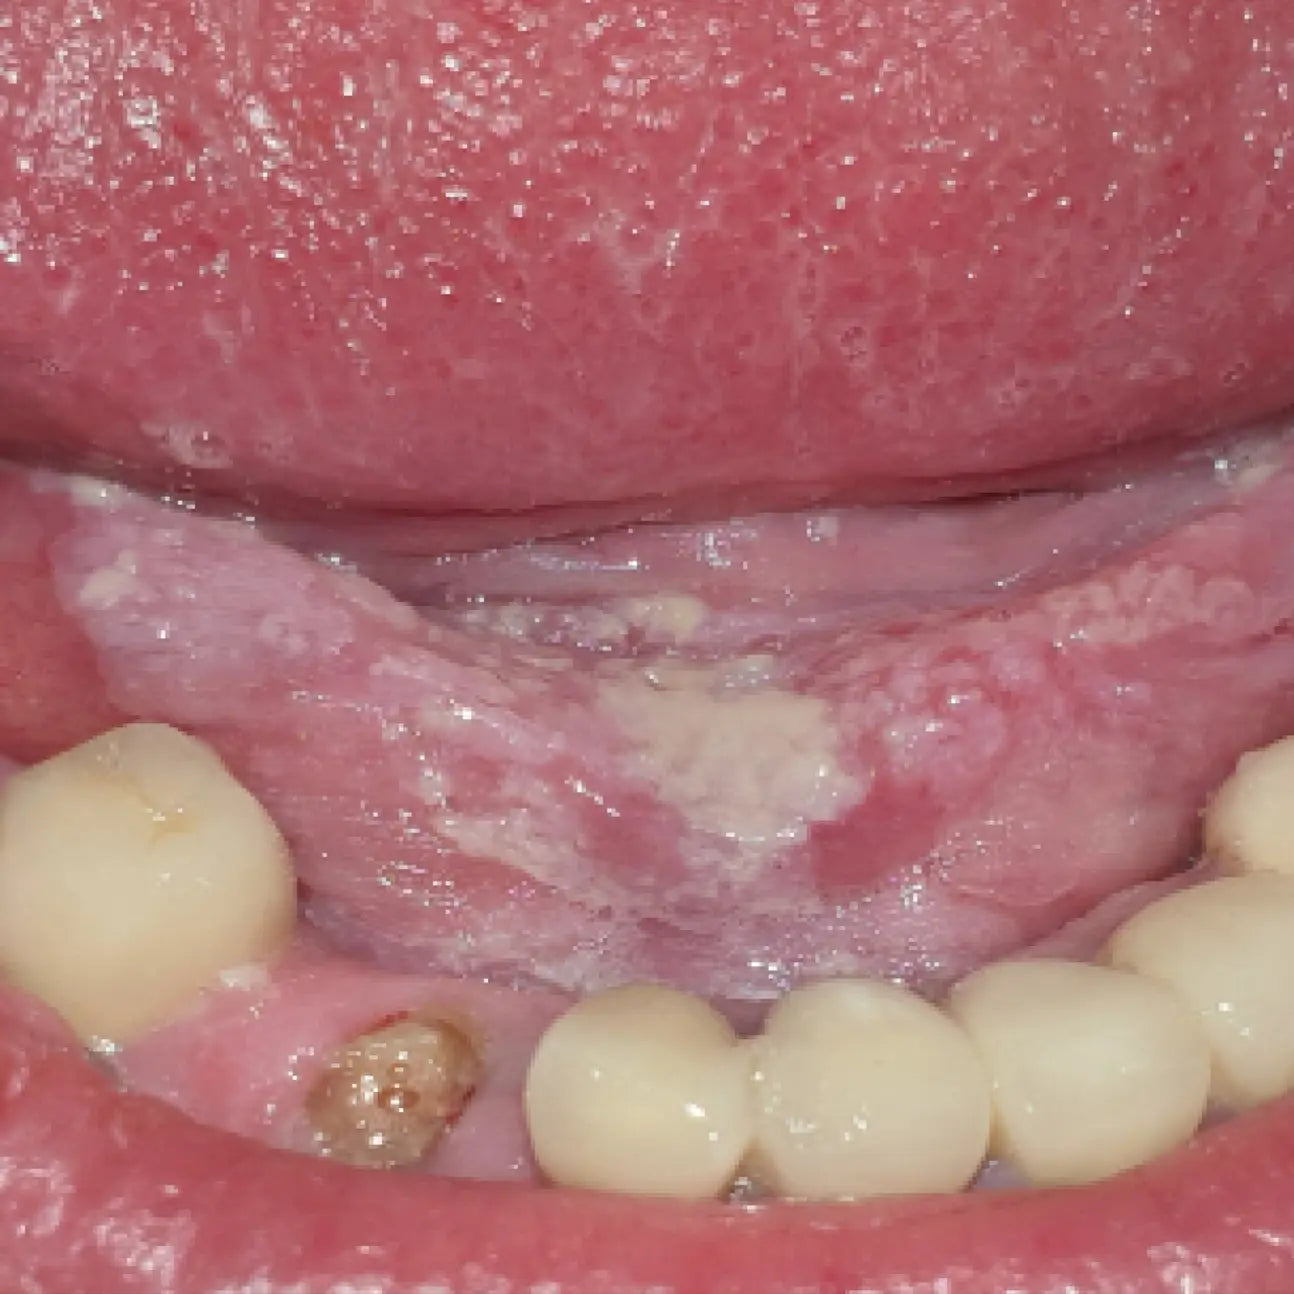

La dermatologie buccale constitue un domaine essentiel mais souvent sous-exploité de la pratique odontologique. La cavité buccale peut révéler de nombreuses lésions muqueuses , bénignes ou éventuellement malignes, d'origine locale ou systémique.

Face à la diversité des manifestations cliniques (ulcérations, leucoplasies, érythèmes, lésions pigmentées, douleurs muqueuses, etc.), le chirurgien-dentiste joue un rôle clé dans le dépistage, le diagnostic précoce et l'orientation thérapeutique .